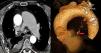

En la actualidad, en la bibliografía solo se encuentran 50 casos de expansión patológica de la arteria bronquial (AAB) con un calibre vascular superior a 2mm1. Mizuguchi et al.2 subrayan que en Inglaterra, hasta el año 2009, tan solo se habían descrito 12 roturas de la AAB. Aún no está claro el abordaje ideal para esta enfermedad. La técnica mínimamente invasiva de embolización endovascular presentó mayor eficacia y seguridad que la toracotomía3,4, pero un método conservador aportaría estabilidad clínica al paciente sin la morbilidad quirúrgica. Presentamos el caso de un varón de 75 años que acudió a urgencias en nuestro hospital con disnea, un episodio aislado de hemoptisis y dolor súbito en el hemitórax derecho. En el año 2009, el paciente tenía diabetes, hipertensión y EPOC y, como consecuencia, se le había realizado un triple bypass coronario. La radiografía torácica mostró un derrame pleural derecho y la toracocentesis demostró el origen de la hemorragia. El paciente estaba hemodinámicamente estable (10g/dl de hemoglobina, presión arterial: 110/70mmHg), pero presentaba una ligera hiperventilación con gasometría normal (SO2: 95,2%, PO2: 90,8mmHg y PCO2: 24,1mmHg) y taquicardia sinusal (115-120 pulsaciones por minuto) en el ECG. Realizamos una toracoscopia videoasistida (VATS) con evacuación de 2.000cc de sangre, aunque no se halló evidencia del origen de la hemorragia en la pleura, el diafragma ni el pulmón. El mediastino tenía aspecto hinchado, convexo, congestionado y con sangre, como demostró la biopsia aspirativa. En las 24h posteriores al procedimiento mínimamente invasivo, se realizó un TAC de sección fina tridimensional (3D-TSCT) torácico en el que se observaba un manifiesto hematoma en el mediastino posterior, una ectasia de las arterias pulmonares predominante en la izquierda (4,6cm) y un aneurisma en la AAB derecha (6×5mm de diámetro) en el contexto del hematoma, probable foco del sangrado anterior. A partir de la evaluación radiológica, decidimos evitar el abordaje quirúrgico y nos decantamos por el tratamiento conservador. Se retiró el drenaje pleural el 4.° día del postoperatorio y se dio el alta al paciente al 6.° día, tras repetir el 3D-TSCT torácico en el que se observó una reducción drástica del hematoma mediastínico. En el seguimiento con 3D-TSCT a los 4 meses, uno y 2 años, destacó la obliteración del aneurisma de la AAB y la resolución total del hemomediastino. La etiología de la AAB parece ser aumento del flujo sanguíneo, hipertensión en la arteria pulmonar o distintas afecciones pulmonares5. Hemos tenido en cuenta diversos factores a la hora de elegir el enfoque conservador: a) detención de la hemorragia al cerrarse el vaso por el hematoma mediastínico; b) cese del derrame hemorrágico en la cavidad pleural tras la VATS; c) revascularización miocárdica previa (mediante la arteria torácica interna izquierda) con fibrosis mediastínica, lo que dificulta el acceso abierto a la AAB, y d) buen estado hemodinámico. Utilizamos la VATS como abordaje de primera línea porque el paciente estaba estable. Además, la taquicardia sinusal y la hiperventilación podían ser síntomas de un empeoramiento general, para lo que se necesita un abordaje urgente inespecífico. La VATS ha demostrado ser una opción ideal para vaciar y limpiar la cavidad pleural. Y nos ha permitido identificar el mediastino como origen de la hemorragia (fig. 1).